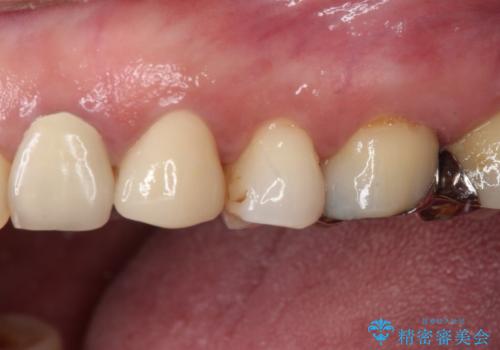

抜歯即時埋入後にはずっと気になっていた排膿が消え、痛みも腫れも特になく、3ヶ月という短期間で無事に治療を終えることができました。